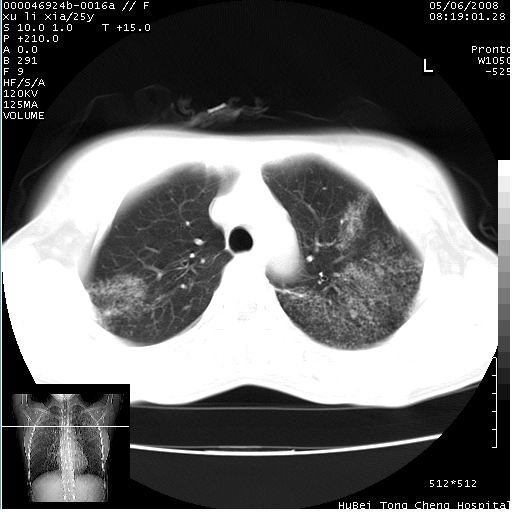

胸部ct轴位平扫(层厚10mm,螺距1.5,重建间隔10mm),图像如下:

(注:上级医院会诊胸部ct片——考虑为肺部真菌感染。)

病灶呈地图样分布于肺外围,与正常组织分界清晰+弥漫性磨玻璃影中见小叶间隔增厚呈碎石路样表现+年轻女性,无明显临床症状=肺泡蛋白沉积症?

双肺上叶可见节段性渗出性病变,可见树芽征像,左肺下叶背段可见结节影。

病灶呈离心性分布,以两上肺多见,远离肺血管纹理,有部分肺间质条索影,病人症状轻微,考虑结节病。